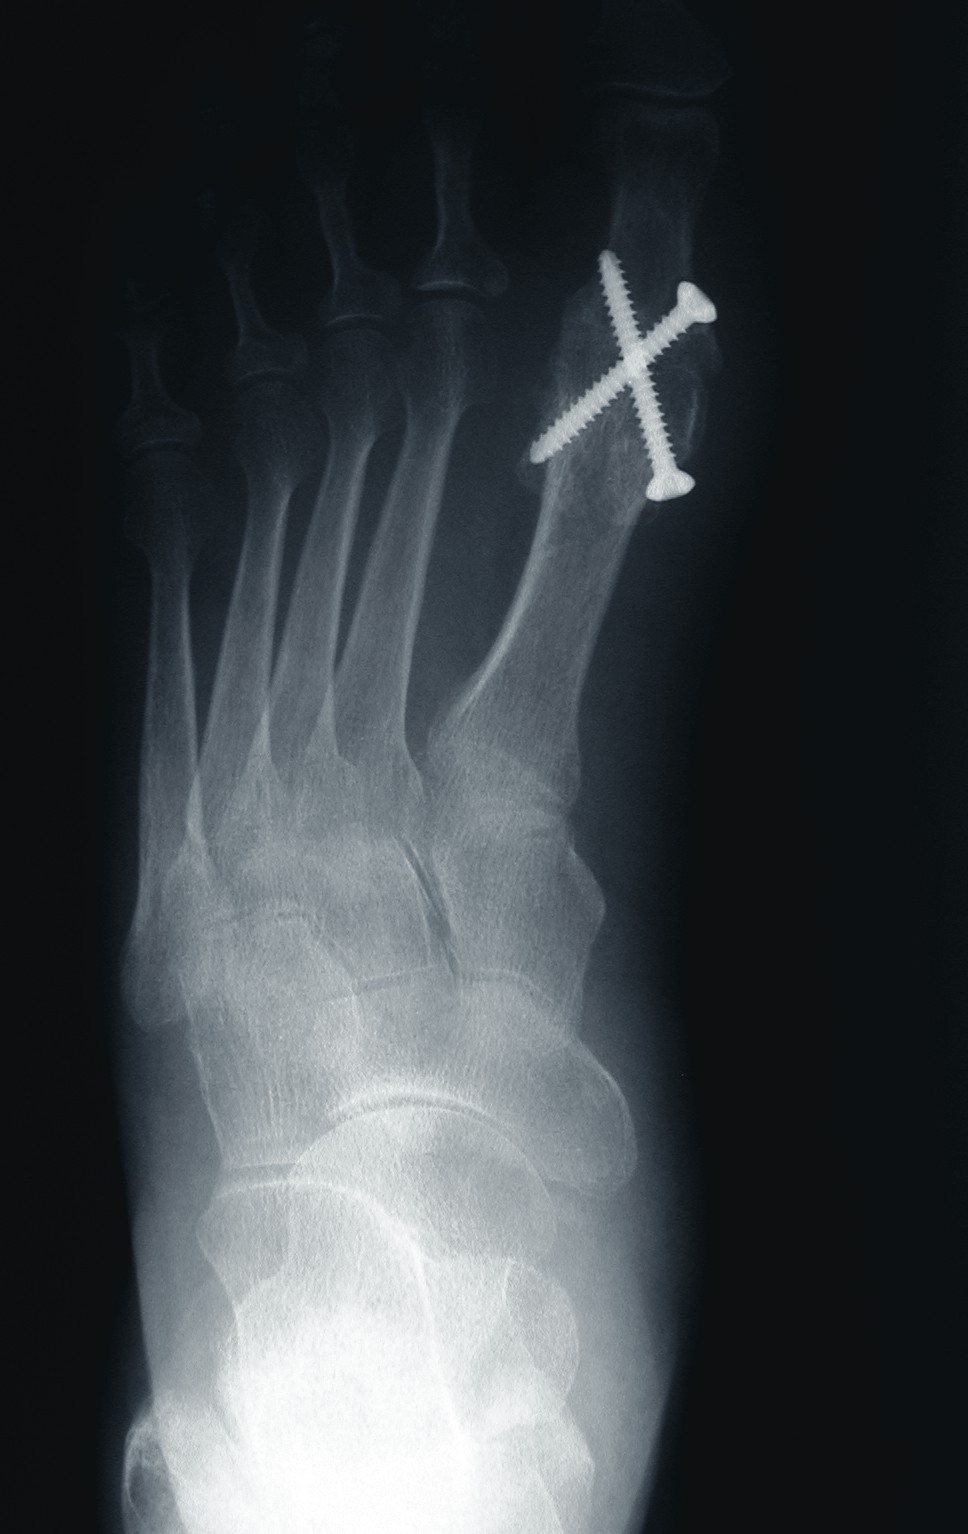

Фотографии процедуры артроэреза подтаранного сустава